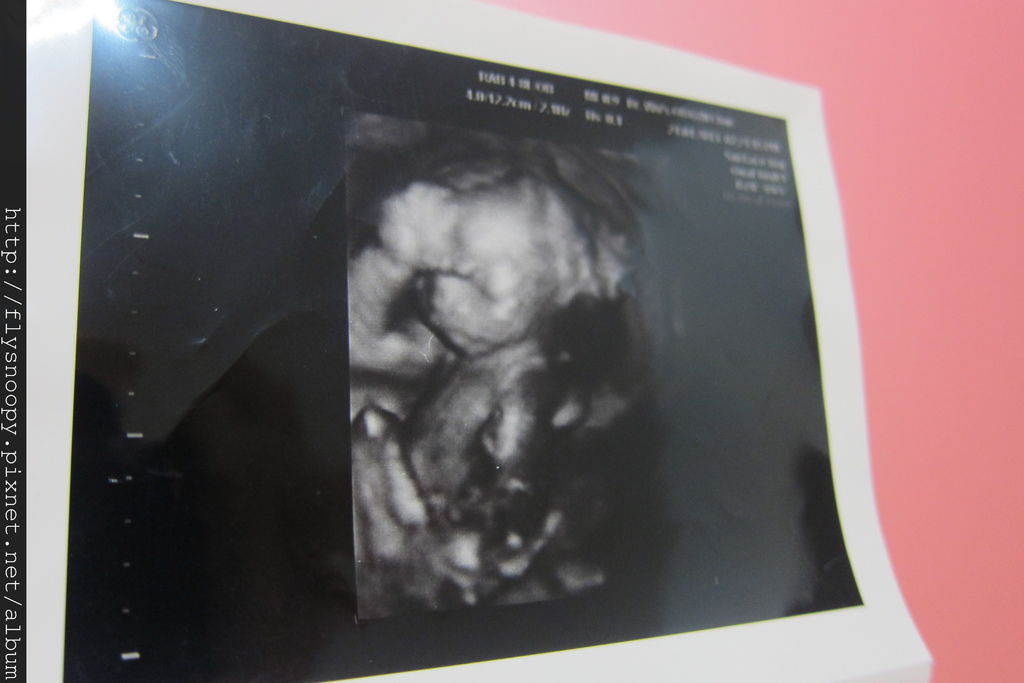

這三張是4/24照的,第一張看得好清楚,她用手摸頭

這次醫生很確定的告訴我們是個小女生喔

上面是4/28照的,可以清楚看見她的眼睛